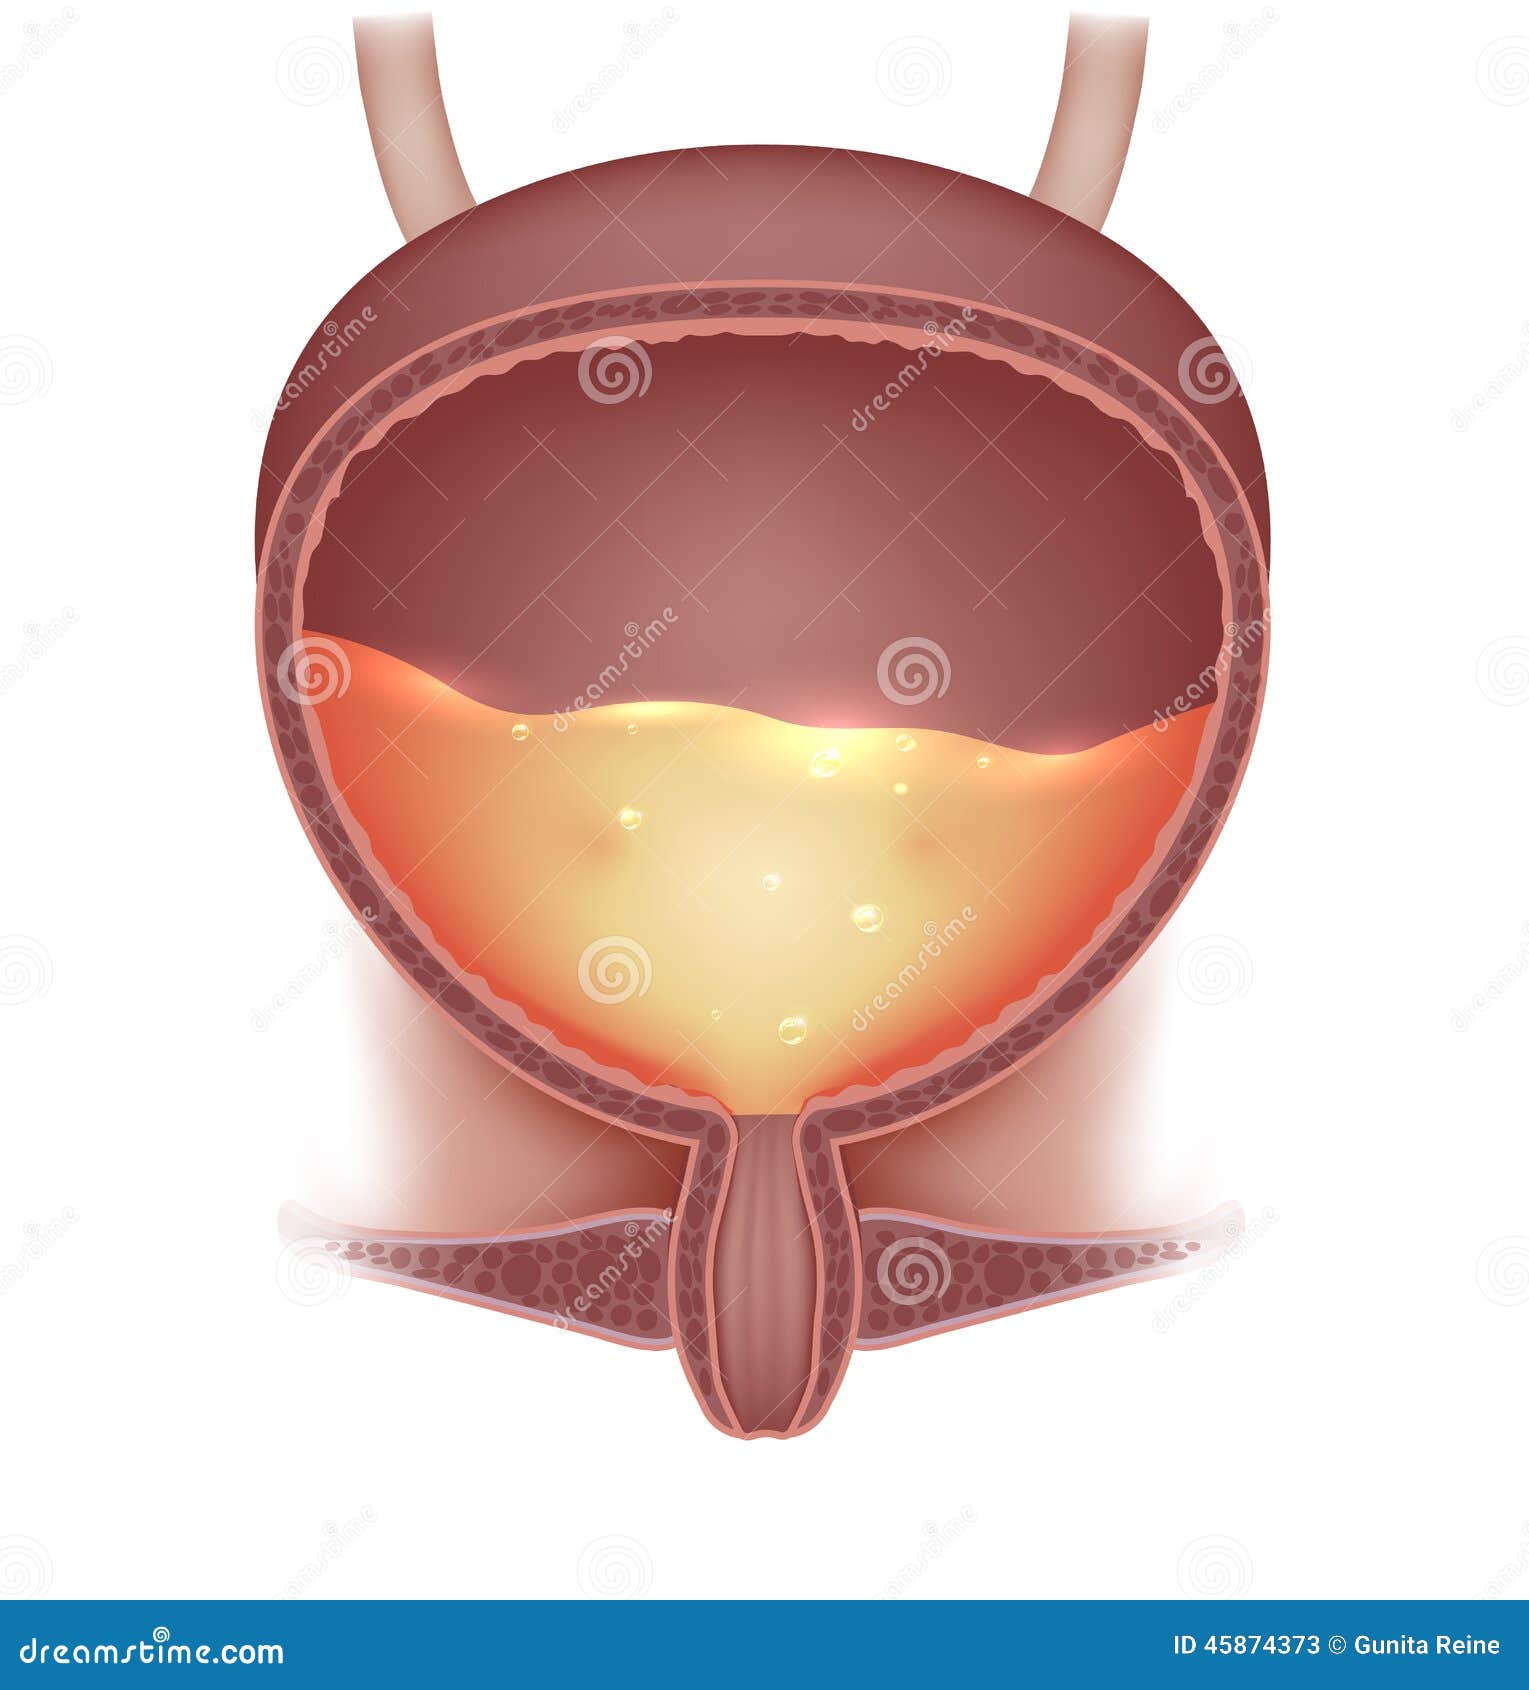

location of the bladder in the human body

Posts: location of the bladder in the human body